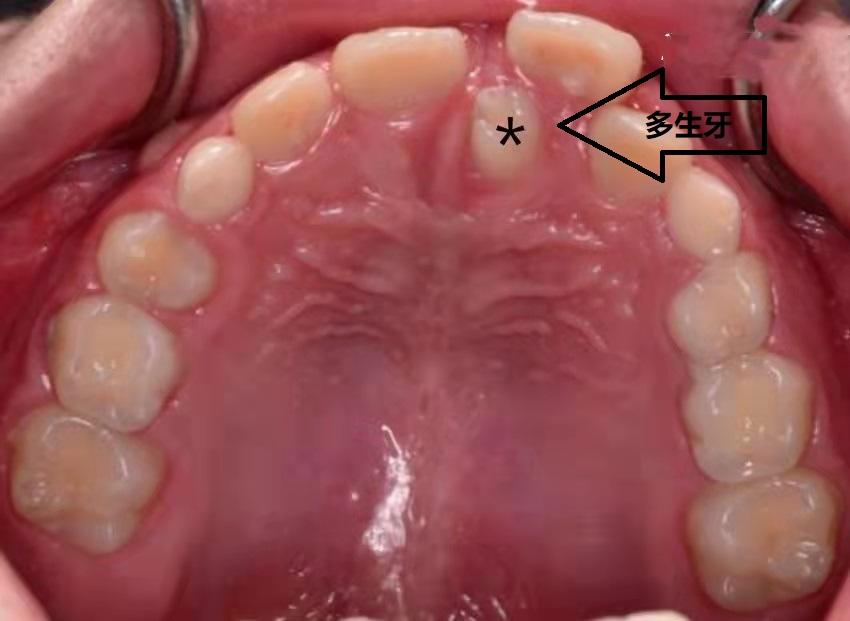

原因三:多生牙

上前牙区是多生牙发生的常见部位,如果多生牙恰好长在了中切牙之间,就会导致中切牙之间的缝隙。部分多生牙生长方向与正常牙齿相同,可以自行萌出;但是大多数多生牙的方向并不与正常牙齿一致,不能自行萌出,只能通过口腔检查拍X光片时发现。如果有多生牙存在,影响了正常牙齿的生长,就需要及时就诊拔除。